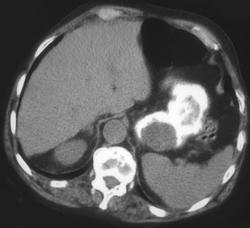

Antral Carcinoma- See Subtle Enhancing Lesion